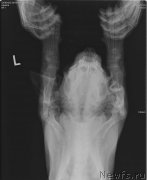

Браунблад МСК Ауди Рэд Лэсс (Brownblood MSK Audi Red Less)

Браунблад МСК Ауди Рэд Лэсс (Brownblood MSK Audi Red Less)